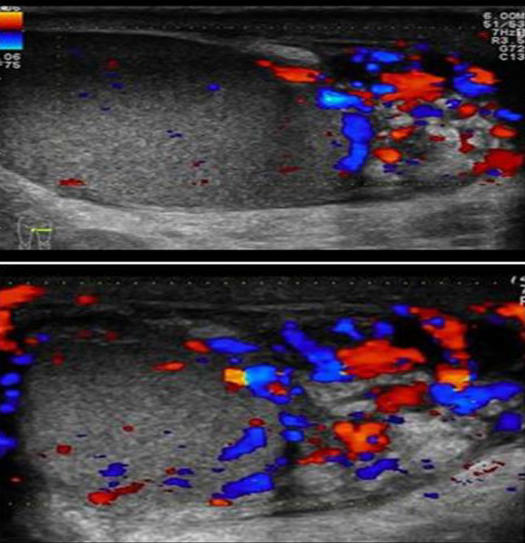

Patient presented with scrotal pain

and swelling - Ranges from mild tenderness to a severe febrile process with acute unilateral scrotal pain. -

A. Give the name of imaging examination. Color Doppler ultrasound

B. Describe the abnormality imaging shows Reactive hydrocele and scrotal wall thickening , edematous epididymis and shows increase vascularity on Doppler

C. What is the most probable diagnosis in the ? Epididymitis

A. Give the name of imaging examination.

*Color Doppler ultrasound is the gold standard investigation.

B. Describe the abnormality

- Hypoechogenicity: Focal or diffuse

- Hypervascularity: Focal or diffuse

- Swelling - Scrotal wall thickening + Scrotal pain and swelling

C. What is the most probable diagnosis in the ? Orchitis